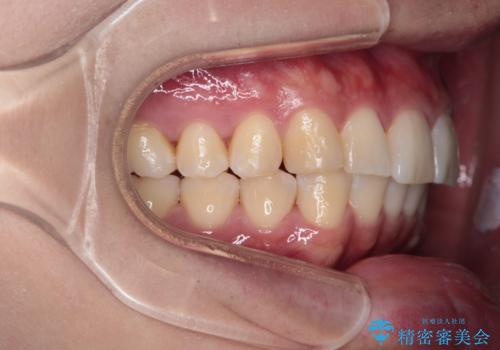

【インビザライン】短期間で出っ歯を治したい

- 出っ歯と口元の突出感が気になるということで来院されました。抜歯矯正も考えられますが、今回は早く終わらせたいという要望があり非抜歯での治療にしました。また遠方から来院されているため、来院回数のおさえられるインビザラインを選択しました。

非抜歯での治療のため、今回はスペース確保のために遠心移動とおもにIPRの処置を取り入れました。